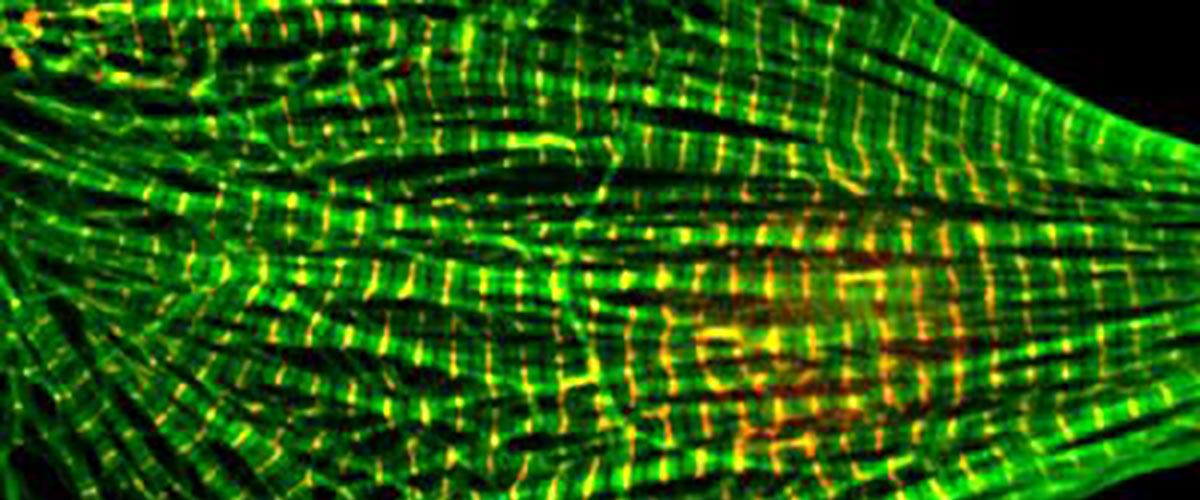

Сердечная мышца состоит из крошечных толстых и тонких нитей белков. Электрические сигналы позволяют этой сложной системе нитей связываться и развязываться в сложной архитектуре, давая мышце возможность сокращаться. Исследование ученых из Университета штата Вашингтон показало, что для идеальной координации между собой, чтобы заставлять сердце биться, длина этих нитей должна быть одинаковой.

Чтобы сердечная мышца оставалась здоровой состоящие из белка актина нити должны иметь длину около микрона, пишет EurekAlert. Например, при кардиомиопатии, которую диагностируют у одного из 500 человек, генетические мутации приводят к слишком короткому или длинному размеру нити.

Чтобы этого не происходило со здоровым сердцем, существуют другие белки, корректирующие правильную длину нитей. Ученые показали, что с одной стороны в этом процессе участвует белок тропомодулин, а с другой — лейомодин. Первый определяет правильный размер нити, а второй корректирует его в случае ошибки.

«Этот молекулярный танец может показаться незначительным, но он играет решающую роль в развитии здорового сердца и других мышц», — пояснили авторы. Это первый раз, когда ученым удалось с такой точностью показать весь процесс. «Ранее несколько лабораторий пытались решить эту проблему, но наши данные, наконец, дают прямое доказательство», — прокомментировал соавтор исследования Дмитрий Толкачев.